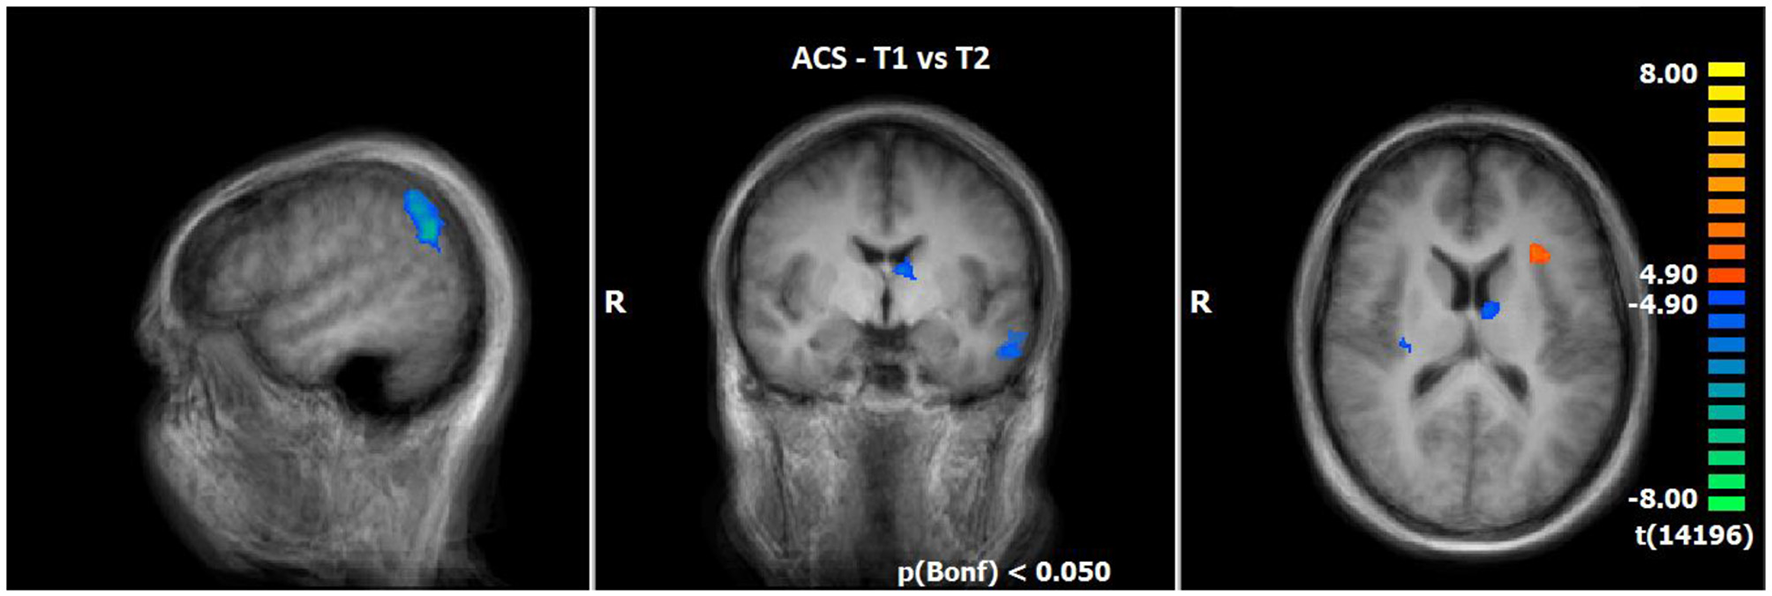

3.2.4 Comparison of neuronal responses of T1 vs. T2 during ACS (N = 14)

The comparison of BOLD responses during ACS before and after therapeutic interventions demonstrated an increased neuronal activity especially in the frontal cortex (including the medial frontal gyrus/middle frontal gyrus/inferior frontal gyrus), parietal areas (e.g., inferior parietal lobule/angular gyrus/supramarginal gyrus), and subcortical areas (e.g. thalamus/anterior nucleus, lentiform gyrus/putamen/claustrum) in T2 as compared to T1. By contrast, neuronal responses were smaller in the left insular cortex (see Table 7; Figure 4).

Figure 4

Comparison of neuronal responses during ACS between T1 and T2 (OCD-related pictures vs. neutral pictures); [p(Bonf) < 0.050, T-score: 4.9–8.0; x = 50; y = −5; z = 15].